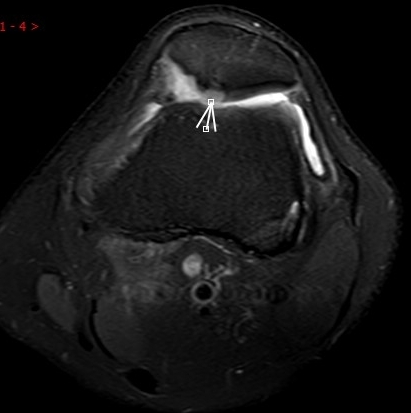

(內(nèi)側(cè)副韌帶損傷)

MRI偵查:揪出前交叉韌帶斷裂(呈“波浪狀”或連續(xù)性中斷)、內(nèi)側(cè)副韌帶損傷,防止關(guān)節(jié)“脫軌”